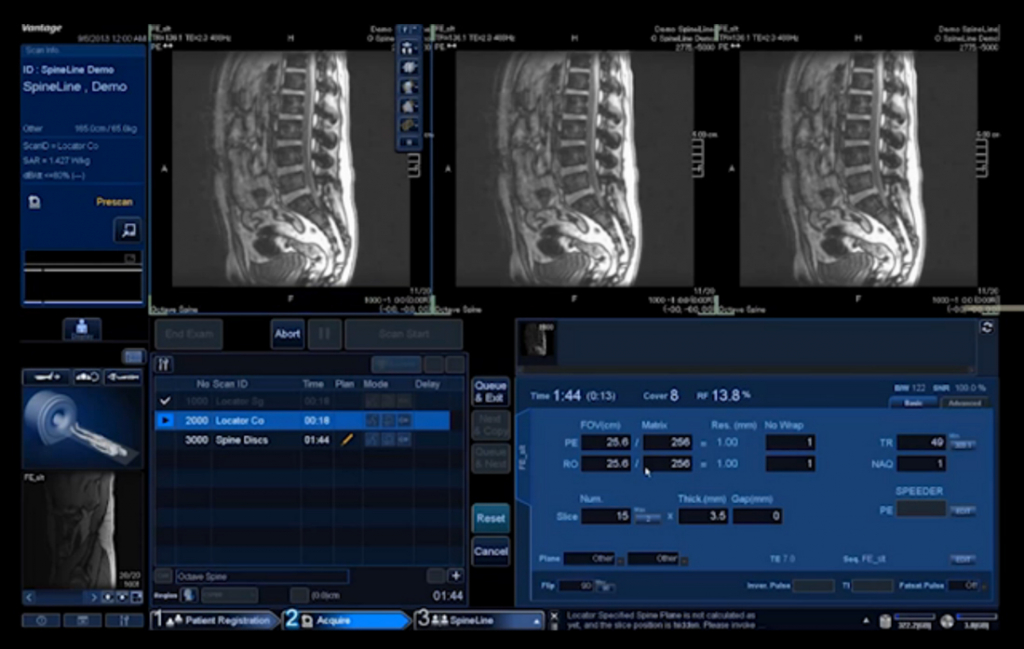

Программная платформа M-Power последнего поколения с интегрированными приложениями облегчает все этапы исследования, начиная с регистрации пациента и заканчивая пост-обработкой и анализом данных. Кроме того, различные приложения помогают правильно позиционировать пациента, например, при спинальных исследованиях или сканировании мозга.

Функционал EasyTech — это полностью автоматическое планирование исследований:

SpineLine - автоматически планирует исследование позвоночника.

- Стандартизирует рабочий процесс с автоматическим позиционированием.Автоматическое определение местоположения позвоночника одним щелчком мыши

- Возможность MPR позволяет регулировать и наклонять срезы

- SpineLine повышает воспроизводимость и эффективность последующих обследований позвоночника